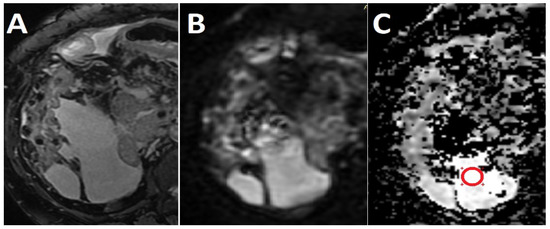

Background and Objective: The imaging differentiation of benign from malignant intraperitoneal collections (IPCs) relies on the tumoral morphological modifications of the peritoneum, which are not always advocating for malignancy. We aimed to assess ascitic fluid with the apparent diffusion coefficient (ADC) to [...] Read more.

Background and Objective: The imaging differentiation of benign from malignant intraperitoneal collections (IPCs) relies on the tumoral morphological modifications of the peritoneum, which are not always advocating for malignancy. We aimed to assess ascitic fluid with the apparent diffusion coefficient (ADC) to determine non-invasive, stand-alone, differentiation criteria for benign and malignant intraperitoneal effusions. Materials and Methods: Sixty-one patients with known IPCs who underwent magnetic resonance examinations for reasons such as tumor staging, undetermined abdominal mass and disease follow up were retrospectively included in this study. All subjects had a final diagnosis of the fluid based on pathological examinations, which were divided into benign (n = 37) and malignant (n = 24) IPCs groups. ADC values were measured separately by two radiologists, and the average values were used for comparing the two groups by consuming the independent samples t-test. The receiver operating characteristic analysis was performed to test the ADC values’ diagnostic ability to distinguish malignant from benign collections. Results: The differentiation between benign and malignant IPCs based on ADC values was statistically significant (p = 0.0034). The mean ADC values were higher for the benign (3.543 × 10−3 mm2/s) than for the malignant group (3.057 × 10−3 mm2/s). The optimum ADC cutoff point for the diagnosis of malignant ascites was <3.241 × 10−3 mm2/s, with a sensitivity of 77.78% and a specificity of 80%. Conclusions: ADC represents a noninvasive and reproducible imaging parameter that may help to assess intraperitoneal collections. Although successful in distinguishing malignant from benign IPCs, further research must be conducted in order to certify if the difference in ADC values is a consequence of the physical characteristics of the ascitic fluids or their appurtenance to a certain histopathological group. Full article